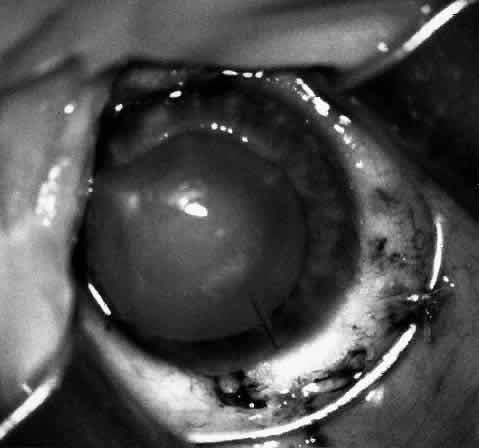

Children who have traumatic cataracts with corneal lacerations are well served by this procedure because the injury often destroys the capsular support that can be used to stabilize an intraocular lens.16–18 The epikeratophakia graft provides structural support for the weakened cornea and minimizes the induced irregular and regular astigmatism, in addition to correcting the optical error (Figs. 3 AND 4).

Fig. 4. Same patient as in Figure 11, with epikeratophakia lenticule in place 3 months after surgery. (Morgan KS, Ellis GS, Marvelli TL, Arffa RC: Epikeratophakia in children. with traumatic cataracts. J Pediatr Ophthalmol Strabismus 23:108–113, 1986)